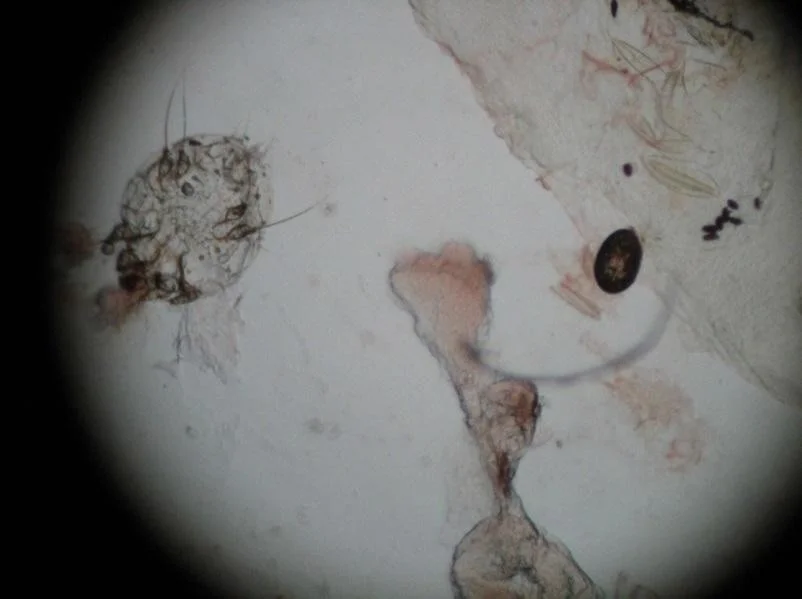

- You perform a mineral oil preparation on the patient.

- You use a 15-blade scalpel and scrape a burrow on the skin. The scraped material is placed on a slide and a drop of mineral oil is added. A cover slip is placed on top and you see the image below when you look through the microscope.

- What do you see?

- scabies mite

- egg

- scybala (feces)